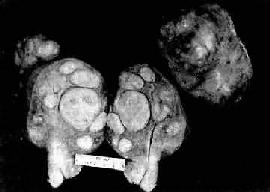

图13-8 子宫体腺(弥漫型)

组织弥漫浸润子宫壁,且部分突入子宫腔中形成大不不等的乳头状肿块